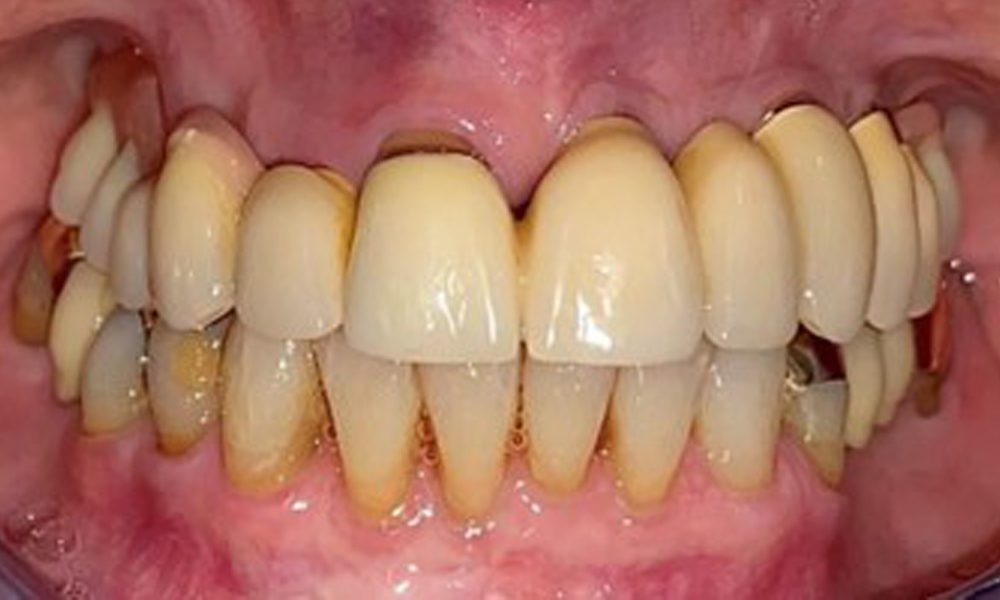

На пациентката е поставена комбинирана подвижна горночелюстна телескопична протеза преди повече от 25 години (фиг. 1, фиг. 2, фиг. 3) и тя е много доволна от протезите си. Пациентката има адекватна фиксирана протеза за долната челюст (фиг. 4).

Денталните открития са следните: Комбинирани снемаеми протези на импланти и телескопични протези, поддържани от зъби, на импланти 15, 13, 21, 23, 24, 25 и зъб 11 (фиг. 1, фиг. 2, фиг. 3). Пациентът е снабден с фиксирана долночелюстна протеза. Над зъби 37-34 и 45-47 бяха налични адекватни мостове (фиг. 4), краищата на коронките бяха интактни и нямаше активен кариес. Върху зъб 43 имаше композитна пломба с маргинална празнина. Имаше рецесия на долната гингива, която разкриваше от 1 до 3 mm от кореновата повърхност. Това се отнася и за 11.